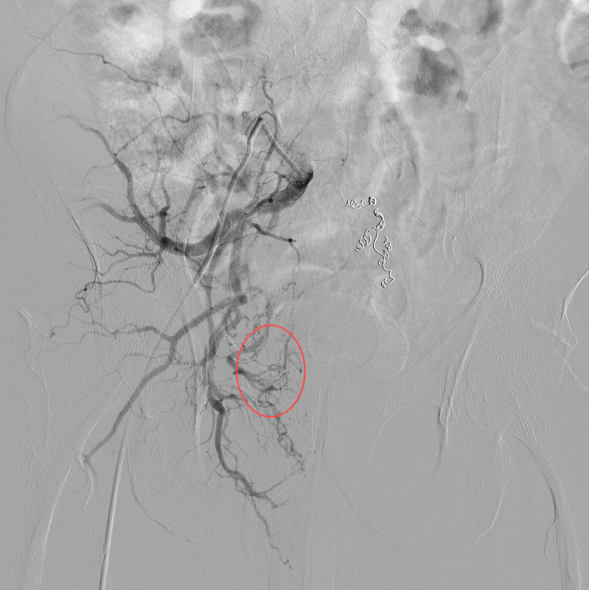

术中髂内动脉造影可见直肠中动脉部分与痔血管相通